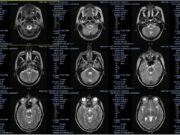

Расшифровка снимков и результатов МРТ онлайн

На сегодняшний день магнитно-резонансная томография и компьютерная томография считаются одними из самых прогрессивных методик проведения диагностики. С их помощью удается получить полную картину состояния...